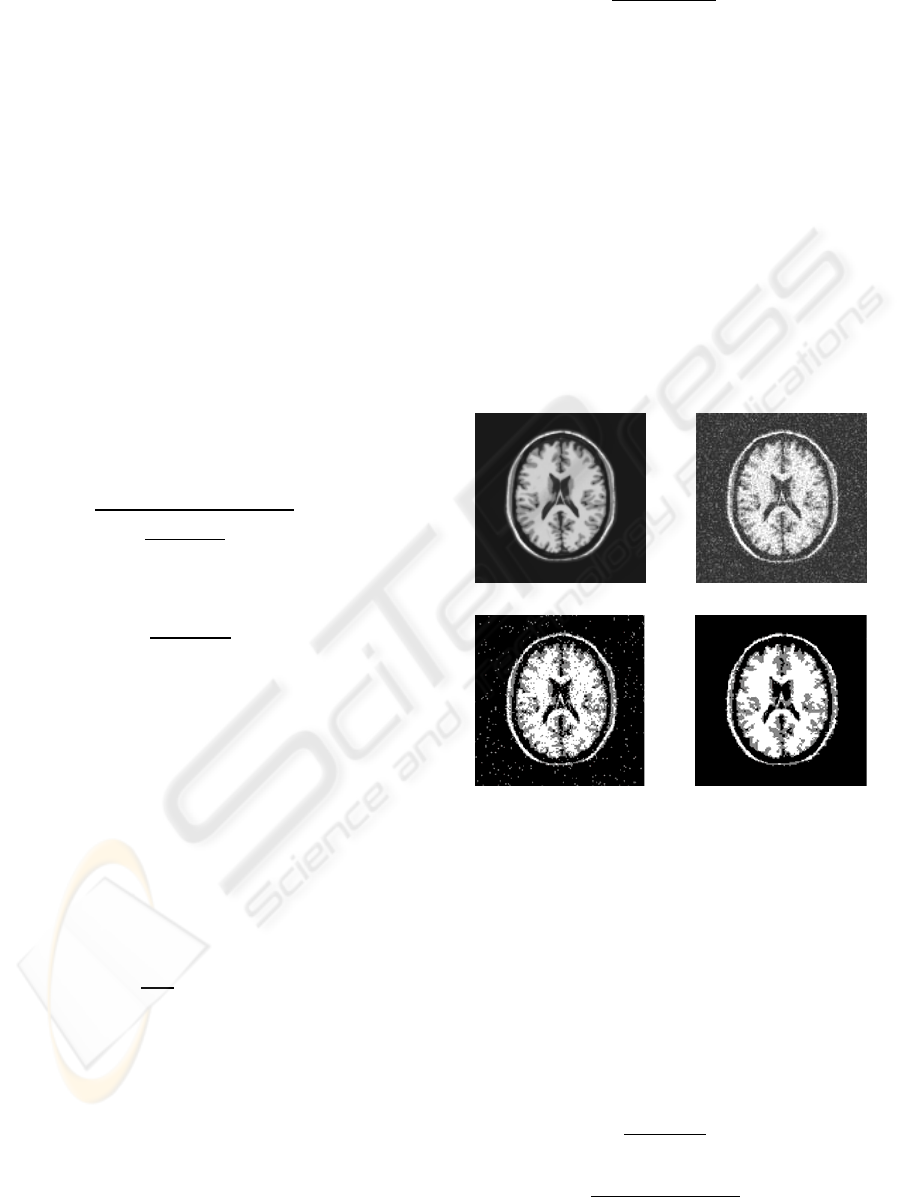

Figure 2: (a) Original image; (b)image with Gaussian

noise, segmented image by (c) FCM; (d ) FCM(α=0.97).